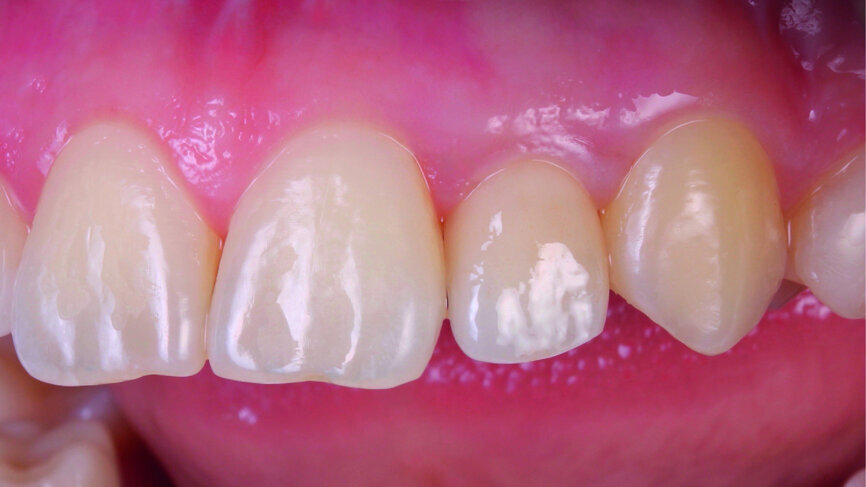

The clinical case features a female patient, who complained about missing tooth #22, as well as the shield-like shape of tooth #12 (Figs. 1 & 2). During the initial examination, the area around the missing tooth was estimated to be quite narrow for an implant. However, the patient declined orthodontic preparation, as she had already previously had orthodontic treatment with orthodontic surgery.

Fig. 1: The patient’s upper teeth before treatment.

Fig. 2: The patient’s upper teeth before treatment.